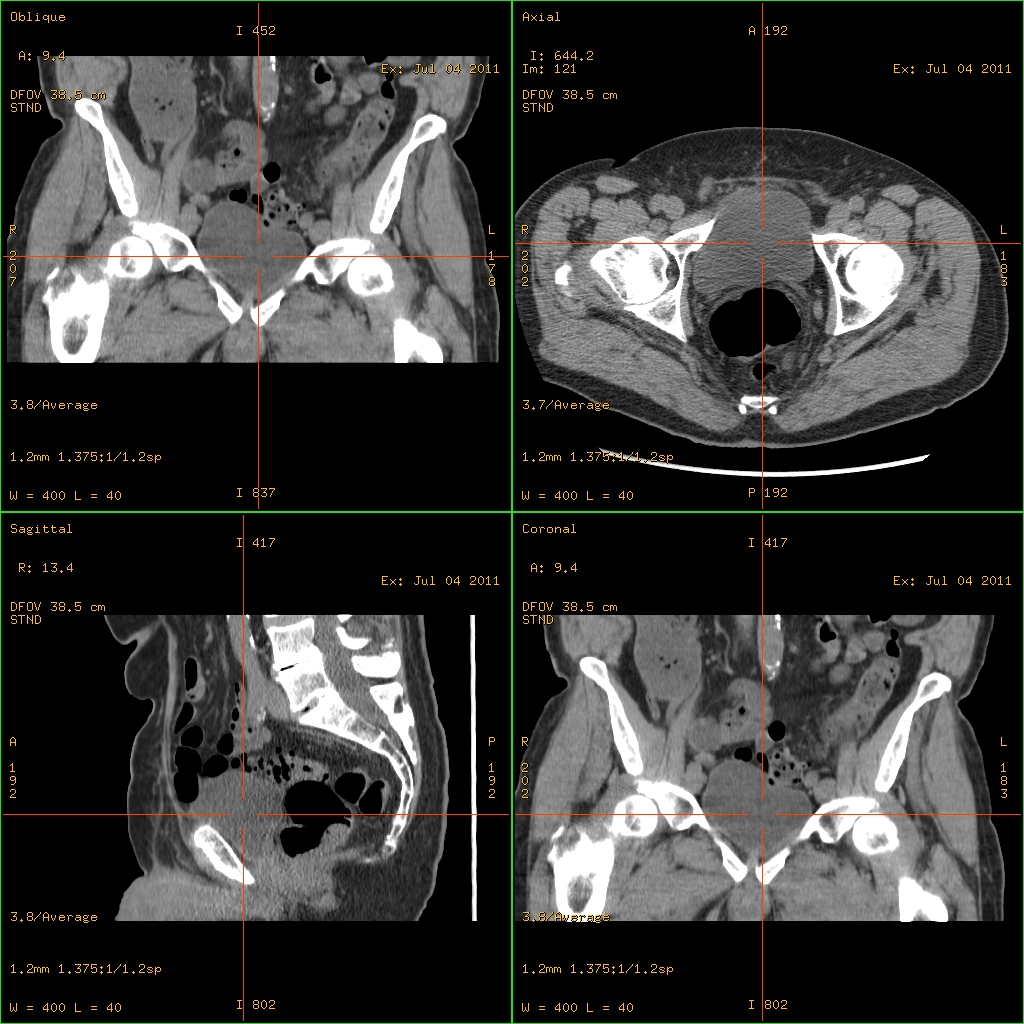

Nach Tierversuchen entsteht 1971 die erste CT-Aufnahme eines Menschen. Ab 1972 auf dem Markt, verbreitet sich das Bildgebungsverfahren zur Transparentmachung und Erfassung innerkörperlicher Strukturen, das im Unterschied zur Röntgentomografie keine störenden Überlagerungen zeigt, rasch vor allem in der medizinischen Diagnostik, aber auch in der Materialwissenschaft. – Johannes Ullmaier